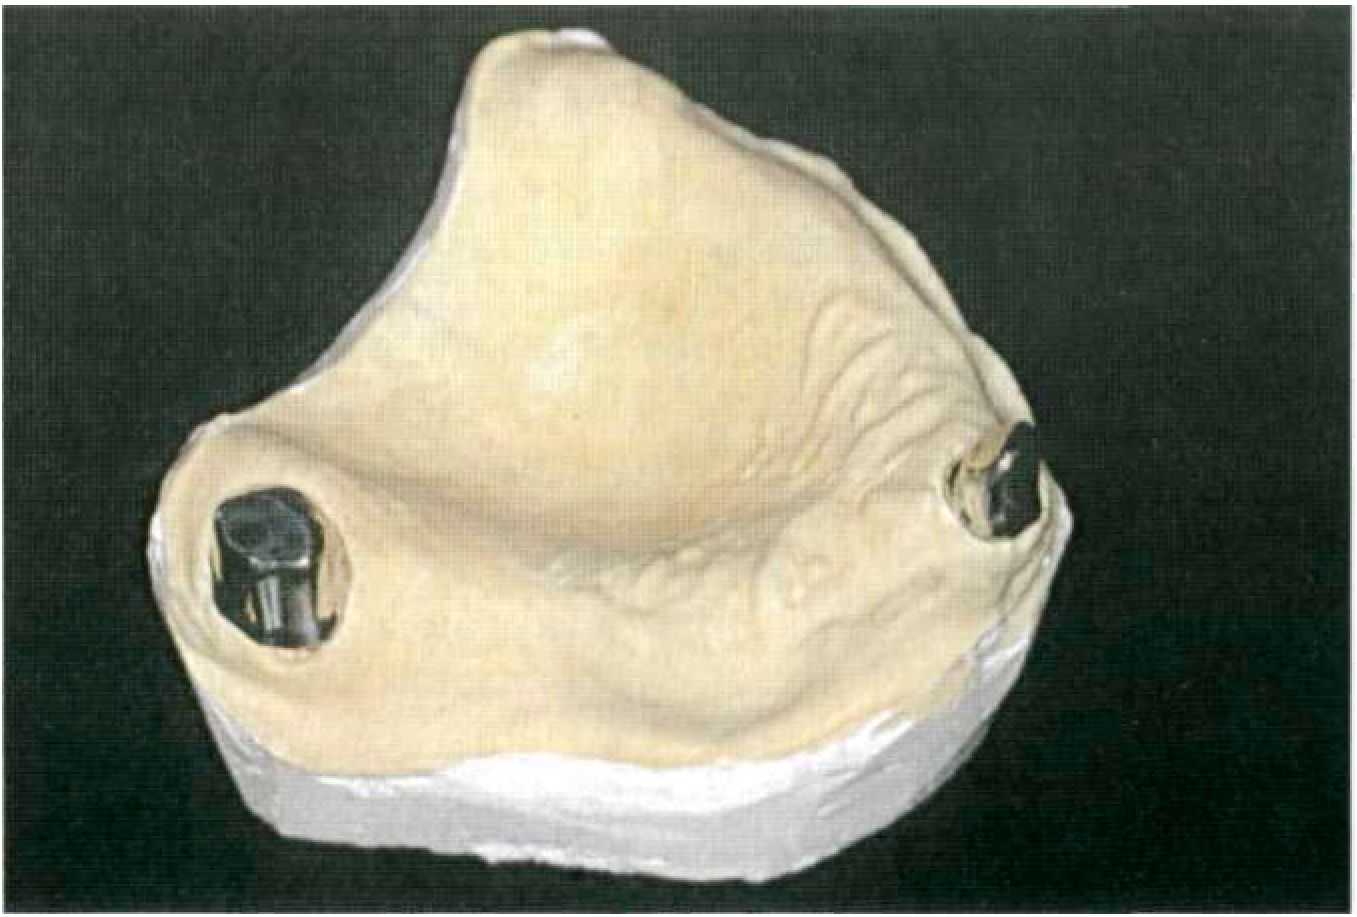

Этап 6. По полученному оттиску зубной техник изготавливает разборную рабочую модель, на которой проводит моделировку первичных коронок с формированием утолщения (1,2 мм) для паза фрикционного штифта (рис. 132). Затем, используя фрезерное устройство, проводится фрезерование до уровня десневого края восковым шабером, имеющим конусность Т (рис. 133). Этап 7. Смоделированную восковую композицию штифтуют и отливают. Для первичных коронок и каркаса покрывного протеза обычно используют один и тот же металлический сплав. После литья первичные коронки припасовывают на модели (рис. 134). Этап 8. В клинике припасовывают первичные коронки на опорных зубах (рис. 135), фиксируют их временно на корригирующую силиконовую оттискную массу и скрепляют коронки между собой пластмассой холодного отверждения, если они находятся в непосредственной близости друг от друга. Для лучшего позиционирования первичной коронки в оттиске, упрощения удержания при припасовке для этого этапа зубной техник оставляет часть литника со сформированной в нем ложбинкой. Оттиск для изготовления металлического каркаса покрывного протеза снимают индивидуальной ложкой аналогичной оттискной массой (рис. 136). Этап 9. Зубной техник подготавливает новую рабочую модель, где четко должны прослеживаться границы будущего покрывного протеза. Затем первичные коронки с помощью специального приспособления переносятся на площадку для фрезерования, где проводится фрезерование твердосплавными фрезами с конусностью Т и закругленным торцом. После фрезерования первичные телескопические коронки полируют тонкодисперсной алмазной пастой (рис. 137). Этап 10. Рабочую модель с первичными коронками готовят к дублированию силиконом и изготавливают огнеупорную модель из специальной массы, например из массы «Deguvest» (рис. 138).

На огнеупорной модели изготавливают восковой каркас съемной части протеза и отливают. Отлитый каркас припасовывают на первичные коронки, ответные вторичные наружные телескопические коронки полируют изнутри мелкодисперсной алмазной пастой и подготавливают всю систему к электроискровой эрозии (рис. 139). Этап 11. Электроискровая эрозия производится на специальном оборудовании фирмы SAE. Рабочую модель с помещенными первичными коронками, закрепленную на рабочем столике, устанавливают в аппарат искровой эрозии (рис. 140). Медный электрод вертикально ориентируют в утолщение, созданное для производства эрозионного паза. Затем на первичных коронках закрепляют каркас съемной части протеза и подают сигнал к началу электроискровой эрозии, которая производится в автоматическом режиме (рис. 141). После проведения электроискровой эрозии зубной техник припасовывает в образовавшиеся пазы фрикционные штифты выбранного диаметра, фиксирует их контактной сваркой к металлическому каркасу съемной части (рис. 142).